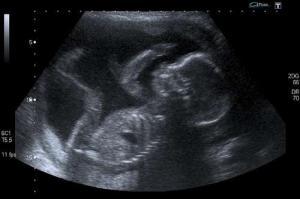

The heartbeat ban would require an examination to determine whether the fetus has a heartbeat or not. If so, an abortion would be prohibited, unless the mother's health is at risk.

"It recognizes that at the sound of a heartbeat, that a child is living," said Rep. Chris Fugate, according to the Associated Press.

"And at the sound of a heartbeat, those who would kill the unborn child would not be allowed to do so anymore. Senate Bill 9 recognizes a heartbeat as a sign of life."

Last month, testimonies were given in front of the Kentucky Senate before votes were cast. April Lanham, a local resident, allowed the heartbeat of her unborn baby to be played through an electronic monitor. Abby Johnson, a former director of a Planned Parenthood clinic and now pro-life activist, also spoke at the event.